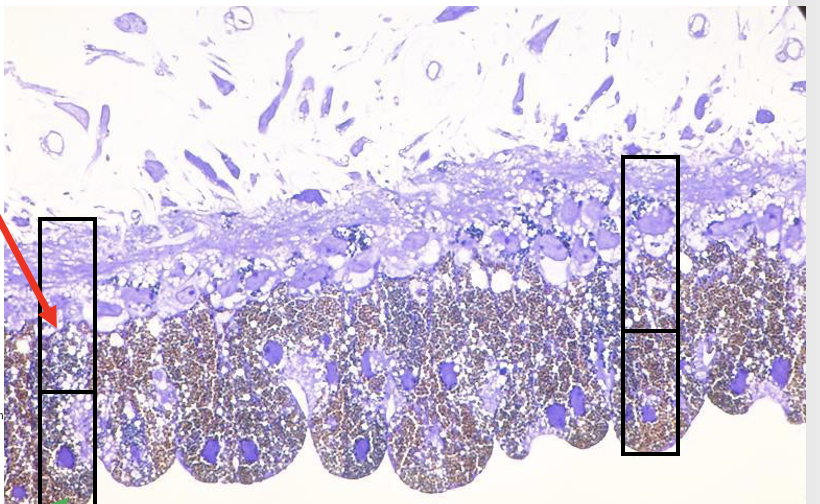

What is this?

Also what is the thing that is stained dark purple?

Quantify the axon diameter

Cross section of cranial nerves

Soma

10 micrometres